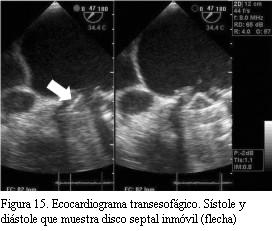

ETE (figura 15): prótesis mitral mecánica con aumento de sus gradientes. Inmovilidad del disco septal con gran cantidad de trombos, algunos móviles. Insuficiencia mitral leve.

Ventrículo derecho dilatado con función sistólica disminuida en grado moderado.

Insuficiencia tricuspídea severa. Presión sistólica de la arteria pulmonar 68 mmHg.

La paciente es valorada por el equipo de cirugía cardíaca y dado el alto riesgo quirúrgico (hipertensión pulmonar severa con disfunción del ventrículo derecho, FEVI disminuida), se decide optar por tratamiento con fibrinolíticos. La paciente fallece por shock cardiogénico refractario horas después.